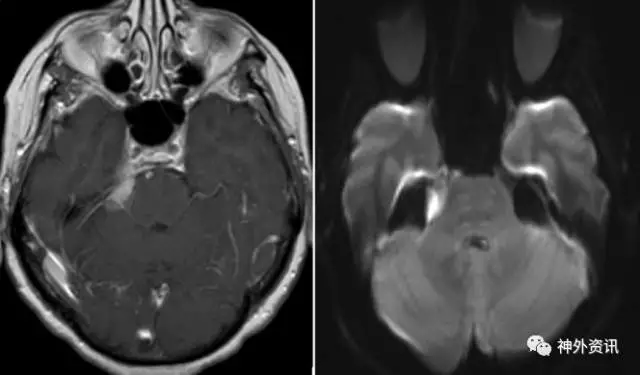

所有准备行微血管减压术的患者需行脑核磁共振成像(MRI)或计算机断层(CT)扫描检查以排除占位性病变如脑膜瘤、听神经瘤和表皮样囊肿。在高分辨率T2W像,常可发现血管环明显压迫三叉神经。

图2:MRI T2W加权像轴位片显示在脑池段血管袢(红色箭头)压迫了右侧三叉神经。